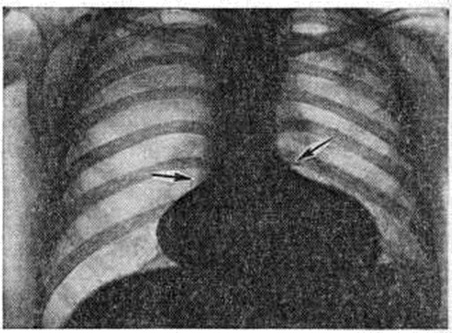

Послеоперационная летальность до 7%. Более чем у половины оперированных сохраняется слабый систолический шум вследствие незначительной регургитации из желудочка. Ок. 80% пациентов в отдалённые сроки после операции практически здоровы. Атриовентрикулярный канал (полная форма). Полный атриовентрикулярный канал (рисунок 6) — сложный Пороки сердца врождённые, при котором, кроме первичного дефекта межпредсердной перегородки и расщепления створок клапанов, имеется и дефект межжелудочковой перегородки, создающий с дефектом межпредсердной перегородки единое отверстие. Этот порок характеризуется преимущественно аномалиями створок клапанов, наличием общего атриовентрикулярного отверстия и подстворочного дефекта различных размеров в межжелудочковой перегородке (рисунок 1, г). Очень редко дефект межпредсердной перегородки закрывается, а аномалия представляет собой сочетание расщепления створки с дефектом межжелудочковой перегородки. Крайняя форма полного атриовентрикулярного канала — большой первичный дефект межпредсердной перегородки, переходящий в большой дефект межжелудочковой перегородки, и единый атриовентрикулярный клапан, в котором половинки правого и левого предсердно-желудочковых клапанов срастаются настолько, что представляют собой переднюю и заднюю створки. При полном атриовентрикулярном канале хорды аномальных створок могут перебрасываться в смежный желудочек, прикрепляться к одной сосочковой мышце. Нарушение гемодинамики обусловлено регургитацией крови из желудочков в предсердия и артериовенозным шунтированием через патологический отверстие в перегородках сердца. При полном атриовентрикулярном канале сердечная недостаточность проявляется уже в первые недели или месяцы жизни. Дети плохо развиваются физически, часто страдают инфекционные болезнями. Возникает одышка (даже в покое), резкая утомляемость, печень и сердце увеличиваются. Выслушивается пансистолический шум над верхушкой сердца и по левому краю грудины. При физических нагрузках появляется лёгкий цианоз. Определяемое расщепление II тона с усилением лёгочного компонента связано с гиперволемией малого круга и блокадой правой ножки пучка Гиса. На ЭКГ — отклонение электрической оси сердца влево. На ФКГ над верхушкой сердца и в четвёртом межреберье слева регистрируется интенсивный систолический шум, связанный с регургитацией крови из желудочков и сбросом крови из левого желудочка в правый. Эхокардиограмма регистрирует необычные движения передней створки митрального клапана, иногда её расщепление и наличие промежутка между ней и межжелудочковой перегородкой. Рентгенологически определяется умеренная или значительная кардиомегалия и дилатация лёгочного ствола (рисунок 7). При катетеризации сердца катетер легко проникает во все его отделы. В правом предсердии обнаруживается артериальная кровь, давление в нем и лёгочном стволе повышено. Отмечается высокое сопротивление лёгочных сосудов. При рентгеноконтрастном исследовании определяется деформация митрального клапана, попадание контрастного вещества в правые отделы сердца, левое предсердие, а также деформация выходного отдела левого желудочка. Лечение лёгочной гипертензии в раннем детском возрасте оперативное: сужение лёгочного ствола; эта паллиативная операция не всегда даёт положительный результат. Радикальная операция, проводимая в условиях искусственного кровообращения, направлена на закрытие дефекта заплатой и восстановление обоих предсердно-желудочковых клапанов. Для проведения коррекции иногда приходится рассекать обе (переднюю и заднюю) створки, чтобы вшить заплату, после чего противолежащие половинки створок фиксируют к заплате и между собой. В тех случаях, когда сухожильные хорды клапана перекидываются в соседний желудочек, для них в заплате оставляют маленькое отверстие или производят иссечение клапана и их протезирование. Большинство больных с полным атриовентрикулярным каналом погибают в раннем детском возрасте. У выживших развивается сердечная недостаточность, лёгочная гипертензия, часто возникают респираторные заболевания. После операций главная причина летальных исходов (около 20%) — неадекватная коррекция порока (сохранение регургитации, сброса крови или сердечная недостаточность в результате необратимости лёгочной гипертензии). У выживших практически всегда выслушивается систолический шум, связанный с небольшой регургитацией. В отдалённые сроки после операции погибает около 10% больных, нередко отмечается остаточная недостаточность либо стеноз митрального или трикуспидального клапана, у 5—10% — полная атриовентрикулярная блокада. Большинство больных чувствуют себя лучше, чем до операции,— уменьшается одышка, они становятся более толерантными к физическим нагрузкам. Уменьшаются размеры сердца и кровенаполнение сосудов лёгких. Гипоплазия правого желудочка обычно сочетается с атрезией лёгочного ствола, его стенозом и атрезией трёхстворчатого клапана. Очень редко порок бывает изолированным. Он является разновидностью аномалии развития правых отделов сердца (трикуспидальной атрезии, аномалии Эбштейна, стеноза и атрезии лёгочного ствола, тетрады Фалло). Наблюдаются две его морфологический формы: правый желудочек с небольшой полостью, резко гипертрофированной стенкой и изменённым трикуспидальным клапаном; правый желудочек с большой полостью, тонкими фиброзно-перерождёнными стенками и неполноценным трёхстворчатым клапаном. Показано наложение кавопульмонального или аортолёгочного анастомоза. Дефекты венозного синуса. При этом Пороки сердца врождённые дефект межпредсердной перегородки локализуется сверху или снизу (полая вена переходит в стенку левого предсердия) и вены лёгкого впадают в верхнюю (нижнюю) полую вену или её устье. Чаще встречаются верхние дефекты венозного синуса. Верхняя полая вена ниже впадения непарной вены значительно расширяется. В неё двумя-тремя стволами вливаются вены верхней доли правого лёгкого, а вены средней доли — в устье полой вены на уровне дефекта перегородки. При нижнем дефекте венозного синуса отмечается транспозиция нижней лёгочной вены вправо, благодаря чему иногда создаётся видимость смещения нижней полой вены в сторону левого предсердия. Отсутствие перегородки между полыми венами со смещением лёгочных вен вправо называют средним дефектом венозного синуса. Размеры дефекта перегородки — от 0,5 до 2 сантиметров. При нижнем дефекте венозного синуса устье нижней лёгочной вены смещено вправо. Клапан нижней полой вены (евстахиева заслонка) иногда, сливаясь с межпредсердной перегородкой в области коронарного синуса, создаёт условия для тока крови из этой вены в левое предсердие. Задняя стенка нижней полой вены переходит в стенку левого предсердия. Нарушения гемодинамики аналогичны тем, которые наблюдаются при вторичном дефекте межпредсердной перегородки. Нижний дефект венозного синуса иногда создаёт условия для направления струи крови из нижней полой вены в левое предсердие. Небольшой венозно-артериальный сброс приводит к появлению слабого цианоза и может быть причиной парадоксальной эмболии (попадания венозного тромба в артерии большого круга кровообращения). Эмболия и абсцессы мозга, инфаркты почек и другие осложнения — следствие парадоксальной эмболии. При транспозиции лёгочных вен кровоток в соответствующей части лёгочной ткани усилен (давление в правом предсердии ниже, чем в левом), что сказывается при физических нагрузках. Эффективный газообмен нарастает слабо из-за увеличения балластно-циркулирующей крови. Клиническая картина характеризуется теми же признаками, что и при вторичном дефекте межпредсердной перегородки. Данные ЭКГ, ФКГ и рентгенологическое исследования аналогичны таковым при дефекте межпредсердной перегородки. Однако аномальное впадение лёгочных вен в верхнюю полую вену рентгенологически можно заподозрить по необычно высоко расположенному корню правого лёгкого на фоне усиления прикорневого рисунка. При катетеризации сердца катетер проводят в аномальную лёгочную вену и через дефект в межпредсердной перегородке — в левое предсердие. В тех случаях, когда катетер провести не удаётся, применяют транссептальную пункцию с введением контрастного вещества в левое предсердие. Для распознавания места впадения лёгочных вен также производят их контрастирование. Направление движения контрастного вещества выявляет нормальное или аномальное впадение лёгочных вен. Лечение оперативное. Дефект венозного синуса устраняют либо на «открытом» сердце с помощью заплаты (рисунок 8) или пластики межпредсердной перегородки и задней стенки верхней полой вены, которые подшивают к правому краю аномальных лёгочных вен, либо на работающем сердце путём разделения расширенной верхней полой вены на два канала с последующим подшиванием места деления к нижнему краю дефекта. В последнем случае после коррекции отток легочно-венозной крови осуществляется через сформированный канал верхней полой вены и дефект межпредсердной перегородки в левое предсердие. Послеоперационная летальность около 1%; в 3—5% случаев наблюдается реканализация дефекта. Отдалённые результаты — 80—90% прооперированных практически здоровы. Дефект межжелудочковой перегородки. Изолированный дефект межжелудочковой перегородки — наиболее частый Пороки сердца врождённые у новорождённых (30—40%). Клинические, признаки порока были описаны П. Ф. Толочиновым в 1874 год и Роже (Н. L. Roger) в 1879 год (Толочинова—Роже болезнь). Нарушения формирования межжелудочковой перегородки возникают в первые три месяца беременности. Приблизительно в 85% случаев дефекты располагаются в перепончатой части межжелудочковой перегородки (рисунок 9 и 1, д), то есть непосредственно под правой коронарной и некоронарной створками клапанов аорты (со стороны левого желудочка), на месте перехода передней в перегородочную створку трёхстворчатого клапана под медиальным рогом наджелудочкового гребня межжелудочковой перегородки (со стороны правого желудочка). Иногда дефекты локализуются непосредственно под правой и частично левой полулунными заслонками клапанов аорты (слева), выше наджелудочков ого гребня под клапаном лёгочного ствола (справа). Чаще отверстия располагаются непосредственно под некоронарной створкой клапанов аорты (слева) и под перегородочной створкой трёхстворчатого клапана (справа) вдоль его фиброзного кольца. Ок. 2% случаев — это мышечная локализация дефектов; при этом могут быть и множественные отверстия. Очень редко наблюдается комбинация мышечной и иной локализации дефекта перегородки. Диаметр дефектов перепончатой части межжелудочковой перегородки варьирует от нескольких миллиметров до 3 см; в основном они круглой или овальной формы. Надгребневые дефекты по величине, как правило, средние и большие (от 7 миллиметров до 2 сантиметров) и также круглые; примыкающие к клапанам аорты и лёгочного ствола — более сложной формы. Дефекты вблизи трёхстворчатого клапана, расположенные вдоль его фиброзного кольца, имеют размеры от нескольких миллиметров до 3—4 сантиметров, форма их различна — от круглой до продольной, от полулунной до треугольной. Мышечные дефекты обычно круглые и небольшие. В кардиохирургии размеры дефекта определяются их отношением к диаметру аорты (средние по величине дефекты имеют в диаметре от ¼ до ½ диаметра аорты). Самые большие дефекты простираются от наджелудочкового гребня вниз и кзади вдоль фиброзного кольца под перегородочную и даже заднюю створки трёхстворчатого клапана. Иногда полностью отсутствует верхняя часть межжелудочковой перегородки и аорта открывается как бы в оба желудочка. Края маленьких дефектов обычно покрыты фиброзной тканью, средних и больших — мышечной (там, где отверстие не примыкает к устью клапанов). Проводящая система сердца (смотри полный свод знаний) — пучок Гиса и его ножки — при высоких подгребневых дефектах проходит по нижнезаднему краю дефекта под эндокардом (со стороны левого желудочка); при задних подстворочных дефектах расположение пучка непостоянное — либо по задне-верхнему, либо по задненижнему краю отверстия. При непосредственной близости средних и больших дефектов к фиброзному кольцу клапанов аорты из-за отсутствия достаточной опоры возникает недостаточность клапанов. Так, при локализации дефекта в перепончатой части перегородки или над наджелудочковым гребнем может возникнуть пролабирование полулунной заслонки клапанов аорты в полость правого желудочка с появлением аортальной регургитации различной степени. В некоторых случаях существование артериовенозного сброса рано приводит к гипертрофии правого желудочка, преимущественно его выходного отдела. Увеличение массы наджелудочкового гребня и передней стенки желудочка формирует подклапанное сужение лёгочного ствола, которое проявляется в момент сокращения желудочка (т. е. в систолу). Градиент давления между входным и выходным отделами желудочка может возрасти настолько, что давление в правом желудочке вначале становится равным давлению в левом, а потом начинает его превышать. Спонтанное закрытие дефекта перегородки благодаря разрастанию фиброзной ткани и рубцеванию, а также прирастание створок трёхстворчатого клапана или клапанов аорты к краям дефекта происходит у 25—50% больных, преимущественно в раннем детском возрасте. Дефект межжелудочковой перегородки может сочетаться с артериальным протоком, дефектом межпредсердной перегородки, коарктацией аорты, врождённым митральным стенозом или митральной недостаточностью, аномальной левой верхней полой веной, впадающей в коронарный синус. Направление и величина шунта на уровне желудочков исключительно зависят от соотношения давления между желудочками в систолу и диастолу. При небольшом и среднего размера дефекте движущей силой шунта является градиент давления между левым и правым желудочками. В этом случае объем сбрасываемой крови будет определяться величиной сопротивления, создаваемого патологический отверстием. Максимальная разница в давлении падает на середину и вторую половину систолы. В эту фазу сокращения возникает наиболее интенсивный кровоток через дефект, что определяет на ФКГ характерную форму систолического шума (с усилением ко II тону). При большом дефекте сопротивление не создаётся. Градиент между желудочками, как правило, невелик. Величина шунта в этом случае зависит только от соотношения сосудистого сопротивления в большом и малом круге кровообращения. Преимущественный кровоток будет в сторону меньшего сопротивления. Кроме того, в систоле происходит сокращение перегородки и соответственно меняются размеры и форма дефекта, его соотношение с внутриполостными структурами (клапанами) и наджелудочковым гребнем, что также влияет на величину шунта. В диастоле и в самом начале систолы направление и величина сброса крови определяются относительной податливостью (эластичностью) желудочковых отделов, диастолическим давлением, асинхронностью сокращений. Артериовенозное шунтирование приводит к возрастанию лёгочного кровотока. Через левое атриовентрикулярное отверстие протекает увеличенное количество крови. В результате возникает перегрузка обоих желудочков и левого предсердия, которая соответствует величине шунта (слева направо). При развитии лёгочной гипертензии объем шунта уменьшается, а позднее, когда давление в правом желудочке начинает превышать давление в левом желудочке, становится преимущественно венозно-артериальным. На этой стадии дилатация левых отделов сердца несколько уменьшается, а правый желудочек резко гипертрофируется. Артериовенозный шунт при дефекте межжелудочковой перегородки оказывает существенное влияние на сосуды малого круга кровообращения. При малом дефекте давление в правом желудочке не повышено, несколько увеличен лёгочный кровоток: на этой стадии легочно-сосудистое сопротивление нормальное. При большом дефекте перегородки оно может быть увеличено, что приводит к развитию лёгочной гипертензии. Объем шунта и соответственно лёгочный кровоток обратно пропорциональны соотношению величин сопротивления в малом и большом кругах кровообращения. Так, например, при отношении менее 0,4 артериовенозный сброс крови может быть большим, а лёгочный кровоток резко увеличенным, что приводит к лёгочной гипертензии гиперволемического характера; если отношение колеблется между 0,4 и 0,7, лёгочный кровоток умеренно увеличен, а лёгочная гипертензия будет смешанного характера — гиперволемическая (т. е. сохранен сброс крови) и гиперкинетическая (т. к. повышено легочно-сосудистое сопротивление). Отношение более 0,7 соответствует уравновешенному или обратному сбросу крови, высокому лёгочному артериальному давлению и уменьшенному лёгочному кровотоку; лёгочная гипертензия гиперкинетическая. Если у здоровых людей физическая нагрузка, сопровождающаяся заметным повышением производительности сердца, приводит к падению легочно-сосудистого сопротивления, то при наличии фиксированного высокого лёгочного сопротивления повышение нагрузки может привести к острой сердечной недостаточности. У больных с дефектом межжелудочковой перегородки и высокой лёгочной гипертензией увеличение минутного объёма сердца означает увеличение венозно-артериального сброса, усиление цианоза и ещё большую потребность в артериальной крови. У большинства больных при небольшом дефекте межжелудочковой перегородки и незначительном артериовенозном шунте клинические, проявлений порока практически не отмечается. При больших дефектах перегородки (в 20% случаев) наблюдается выраженная клинические, картина. У новорождённых при большом дефекте перегородки и высоком легочно-сосудистом сопротивлении быстро возникает острая сердечная недостаточность, которая может стать хронической; наблюдается физическое недоразвитие. У новорождённых с эмбриональным типом сосудов, высоким сосудистым сопротивлением, гиперкинетической лёгочной гипертензией, являющихся необратимыми, превышением давления в правом желудочке по сравнению с левым наступает венозно-артериальный сброс крови, приводящий к появлению цианоза и эритроцитоза (смотри полный свод знаний). Такое сочетание гемодинамических и клинические, изменений, развивающихся при дефекте межжелудочковой перегородки, носит название комплекса Эйзенменгера. Новорожденные с большим дефектом перегородки, незначительно увеличенным легочно-сосудистым сопротивлением и лёгочной гипертензией гиперволемического характера также отстают в физическом развитии и плохо переносят физические нагрузки. Если на протяжении первых лет жизни не происходит спонтанного закрытия дефекта или его уменьшения, то к 20 годам лёгочная гипертензия становится гиперкинетической и необратимой, развивается комплекс Эйзенменгера. Появляются вначале при нагрузках, позднее постоянно цианоз, эритроцитоз, венозно-артериальный шунт. В некоторых случаях легочно-сосудистое сопротивление не повышается и наблюдается хронический сердечная недостаточность. У части больных развивается бактериальный эндокардит (смотри полный свод знаний). Таким образом, клинические, картина порока имеет прямую зависимость от размеров дефекта перегородки, величины лёгочного кровотока и степени лёгочной гипертензии. При небольшом дефекте перегородки над сердцем в третьем-четвёртом межреберье по левому краю грудины наблюдается дрожание и выслушивается интенсивный систолический шум, хотя со стороны больного жалобы отсутствуют. Дети со средним и большим дефектом перегородки часто жалуются на одышку при умеренных физических нагрузках и повышенную утомляемость. При физикальном обследовании выявляется увеличенное сердце, отчётливое дрожание и выраженный пансистолический шум с максимумом в четвёртом межреберье по левому краю грудины. Верхушечный толчок усилен. Над верхушкой сердца — лёгкий протодиастолический шум. II тон расщеплен (при отсутствии лёгочной гипертензии), его лёгочный компонент может быть усилен. У больных с аортальной недостаточностью (вследствие пролабирования створки клапанов аорты) прослушивается протодиастолический шум над аортой в третьем-четвёртом межреберье слева от грудины. Нередко имеются признаки сердечной недостаточности (тахикардия, одышка, гепатомегалия, отеки), которую усиливают сопутствующие Пороки сердца врождённые Присоединяются нарушения сердечного ритма. При декомпенсации несколько ослабевают систолический шум и II тон. Для больных с крайней степенью лёгочной гипертензии характерен слабый систолический шум и резко усиленный монофазный тон. На ЭКГ отмечаются признаки левожелудочковой гипертрофии. При большом артериовенозном шунте и развитии лёгочной гипертензии оба желудочка гипертрофированы. С нарастанием лёгочной гипертензии увеличиваются зубцы R в правых прекардиальных отведениях. При комплексе Эйзенменгера — картина выраженной систолической перегрузки правого желудочка. При рентгенологическое исследовании у больных со средними и большими дефектами перегородки находят увеличение обоих желудочков, усиление лёгочного рисунка в прикорневых отделах лёгких и расширение тени лёгочных сосудов (рисунок 10). С развитием лёгочной гипертензии размеры сердца несколько сокращаются, начинает выбухать дуга лёгочного ствола, ослабляется периферический лёгочный рисунок, резко гипертрофирован и увеличен правый желудочек. При катетеризации сердца катетер нередко удаётся провести из правого желудочка через дефект межжелудочковой перегородки в аорту. Измерение давления в правых отделах сердца и лёгочном стволе позволяет оценить степень и обратимость нарушений гемодинамики. Сброс крови через межжелудочковый дефект устанавливают либо исследованием крови на насыщение кислородом, либо красочными, термодилюционными, платиноводородными пробами. Дефект перегородки обнаруживается при контрастировании левого желудочка. Для этого катетер проводят ретроградно по Сельдингеру в корень аорты. Подтягивают проволочный проводник на несколько сантиметров, благодаря чему конец зонда становится менее упругим и его изгибают. После этого катетер благодаря наличию кривизны располагается по центру аорты и сравнительно легко проводится в полость левого желудочка. Этот момент может сопровождаться появлением групповых экстрасистол. Рентгеноконтрастное исследование предпочтительно выполнить в левой косой или боковой проекциях. Через катетер в полость левого желудочка с помощью автоматического шприца под давлением 1 ½—2 атмосфер в течение нескольких секунд вводят максимально возможное количество контрастного вещества. Это приводит к «тугому» заполнению контрастной массой полости левого желудочка, что даёт возможность оценить динамику сокращения левого желудочка и его опорожнение. При этом становится хорошо видимой аорта с коронарными сосудами и патологический сообщение с правым желудочком. Если удаётся достичь в момент съёмки сагитального расположения межжелудочковой перегородки в области дефекта, то диаметр сбрасываемой струи контрастного вещества в правый желудочек будет соответствовать диаметру дефекта. Чаще всего шунтирование происходит на уровне выходного отдела левого и правого желудочка и контрастная масса практически сразу после попадания в правый желудочек оказывается в лёгочном стволе. Таким образом контрастирование левого желудочка позволяет соотнести размеры аорты и лёгочного ствола. По плотности их контрастирования можно судить и о величине артериовенозного шунтирования. Информативность скоростной рентгеновской съёмки (киноангиокардиографии) значительно выше обычной (крупноформатной) съёмки. Она позволяет более детально оценить морфологию порока, динамику сброса крови в различные моменты фазы сердечного сокращения и другие особенности морфологии и гемодинамики (например, множественность дефектов или необычность их локализации, двухсторонний характер сброса контрастного вещества при больших дефектах и развитии лёгочной гипертензии, преобладание венозно-артериального шунтирования). Дифференциальную диагностику проводят с пороками, сопровождающимися артериовенозным сбросом крови (артериальным протоком, аортолёгочным свищом, прорывом аневризмы синуса Вальсальвы и другие). Катетеризация и контрастирование сердца позволяют установить окончательный диагноз. Показания к оперативному лечению возникают при величине артериовенозного шунтирования, превышающей 30—35% минутного объёма малого круга кровообращения. Если больной страдает бактериальным эндокардитом, который протекает хронически, с тенденцией к частым обострениям, несмотря на активную медикаментозную терапию, показания к операции могут быть расширены. У новорождённых и детей в возрасте до 3 лет в связи с острой сердечной недостаточностью могут возникнуть показания к неотложной коррекции порока. В некоторых случаях при формирующейся лёгочной гипертензии и тяжёлом общем состоянии ребёнка оправдано оперативное вмешательство с целью сужения лёгочного ствола. При сопутствующих других Пороки сердца врождённые коррекция пороков может быть расчленена на два этапа: вначале устраняют открытый артериальный проток, коарктацию аорты и другие, а затем дефект межжелудочковой перегородки. Закрытие дефекта межжелудочковой перегородки осуществляют в условиях искусственного кровообращения. Доступ — срединная стернотомия или правосторонняя торакотомия с пересечением грудины. Подход к межжелудочковой перегородке зависит от локализации дефекта: надгребневые и мышечные (возле верхушки сердца) удобнее оперировать через стенку правого желудочка (поперечная, косая вентрикулотомия), подгребневые, задние подстворочные, а также мышечные вблизи от фиброзного кольца трёхстворчатого клапана — через стенку правого предсердия (атриотомия). Если дефект межжелудочковой перегородки сочетается с аортальной недостаточностью, то подход может быть чрезаортальным. В этом случае при невозможности сохранить клапаны аорты (вследствие их большой деформации) одну из створок клапанов надсекают по комиссурам и подшивают к краям дефекта. Аортальный клапан протезируют. Однако в некоторых случаях закрытие дефекта заплатой (со стороны правого желудочка) создаёт опору клапану аорты, в результате исчезает или уменьшается регургитация из аорты (то есть протезирования клапанов не требуется). Уже во время операции (после герметичного закрытия дефекта) систолический шум полностью исчезает (рисунок 11). Небольшие дефекты межжелудочковой перегородки ушивают, причём наиболее надёжными являются П-образные швы с прокладками. Почти в 80% случаев средних и больших дефектов необходимо пластическое закрытие отверстия заплатами из аутоперикарда или полимерных материалов (смотри полный свод знаний). Более предпочтительно подшивание заплаты матрацным швом со стороны левого желудочка. Для этого после наложения швов на заплату и края дефекта, заплату опускают через отверстие в левый желудочек, швы подтягивают и связывают между собой. Рассекать створку трёхстворчатого клапана не требуется. Профилактика повреждения проводящих путей заключается в наложении швов на некотором расстоянии от края дефекта, где проходит пучок и ножки пучка Гиса. Множественные мышечные дефекты закрывают после правожелудочковой или левожелудочковой вентрикулотомии общей заплатой из аутоперикарда или подшиванием участка стенки желудочка к краям дефекта. При сочетании подклапанного стеноза лёгочного ствола с дефектом перепончатого отдела межжелудочковой перегородки возможно закрытие отверстия мышечным лоскутом, выкроенным из наджелудочкового гребня.